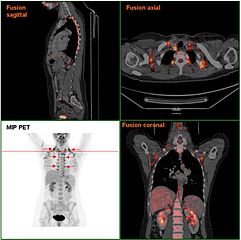

« Nous avons identifié une troisième variété de cellules graisseuses. Il y avait les blanches et les brunes, et maintenant, on sait qu’il en existe un autre type, beige, présent chez presque tous les êtres humains », explique le biologiste Bruce Spiegelman qui a supervisé l’étude. Ces cellules beiges – que l’on retrouve dans des dépôts de la taille d’une noix situés sous la peau, près des clavicules et le long de la colonne vertébrale – ont pour principale fonction la production de chaleur (thermogenèse) ; ce qui les distingue des adipocytes blancs, qui servent essentiellement au stockage des graisses… dont l’excès conduit à l’obésité. Du point de vue fonctionnel, ils sont en revanche assez similaires aux adipocytes bruns dont on pensait jusqu’à peu qu’ils n’étaient présents que chez le nouveau-né et les mammifères hibernants qu’ils protégeaient contre les effets du froid.